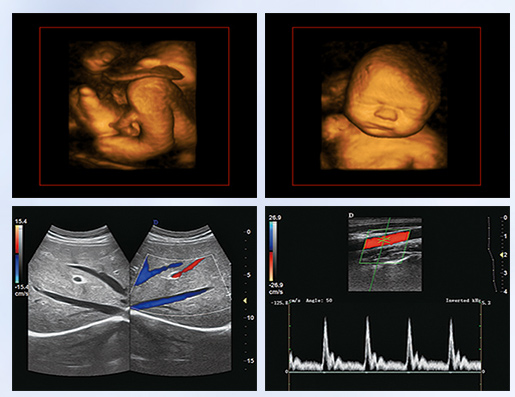

超聲學(xué)科的發(fā)展史,猶如一卷悠遠(yuǎn)綿長(zhǎng)的畫(huà)冊(cè)。從黑白B超機(jī)到彩超機(jī),從一維、二維向三維立體動(dòng)態(tài),從推車式B超機(jī)到便攜式彩超機(jī),從觀察人體解剖學(xué)到分析人體組織內(nèi)細(xì)微結(jié)構(gòu)和功能。隨著科學(xué)技術(shù)的不斷發(fā)展,B超機(jī)功能也越來(lái)越方便強(qiáng)大。

超聲作為一門醫(yī)、理、工相結(jié)合的學(xué)科,涵蓋超聲診斷、超聲治療和超聲工程技術(shù)等門類,其在臨床診斷和治療中發(fā)揮著日益重要的作用。B超機(jī)借助各種超聲探頭,以精湛的技術(shù)和嚴(yán)謹(jǐn)?shù)膽B(tài)度掃描著人體臟器內(nèi)的細(xì)微病變,給臨床提供準(zhǔn)確而快捷的檢查報(bào)告,在影影綽綽間,發(fā)現(xiàn)病魔的蛛絲馬跡中,用“金睛火眼”挽救患者性命……超聲的每一幅圖像,都是靠超聲醫(yī)生親自探查并采集的,每一個(gè)患者,至少都有10張以上的圖像存儲(chǔ),對(duì)于比較復(fù)雜的病例,有幾十甚至上百?gòu)垺6宜械膱D像,都需要超聲醫(yī)生在邊探查的時(shí)候,邊思考分析。這,是一個(gè)真正手腦并用的工作。